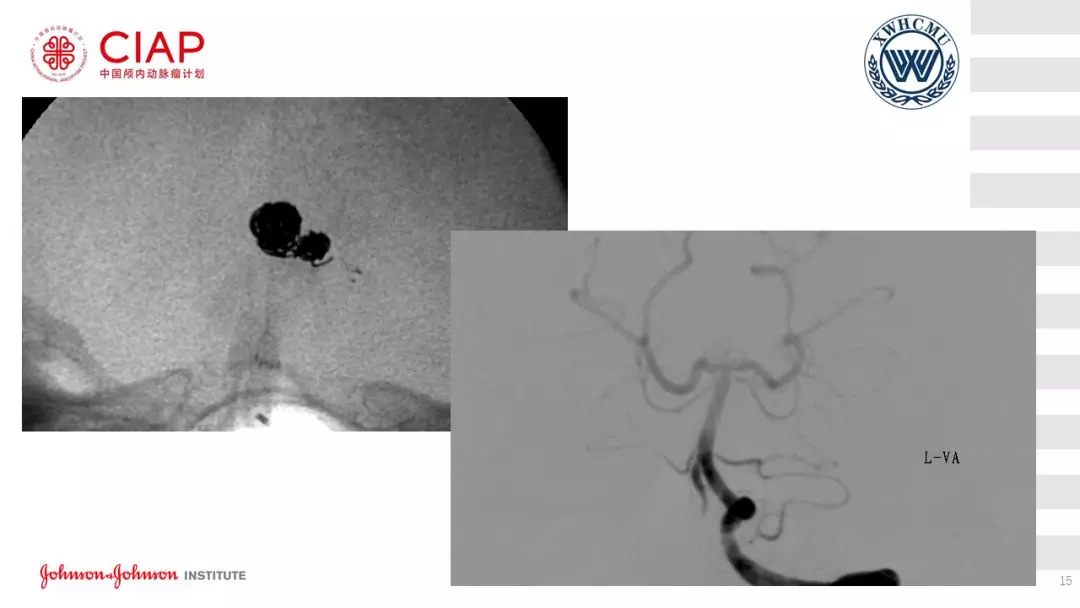

张鹏教授:不同辅助方法下栓塞动脉瘤弹簧圈的选择